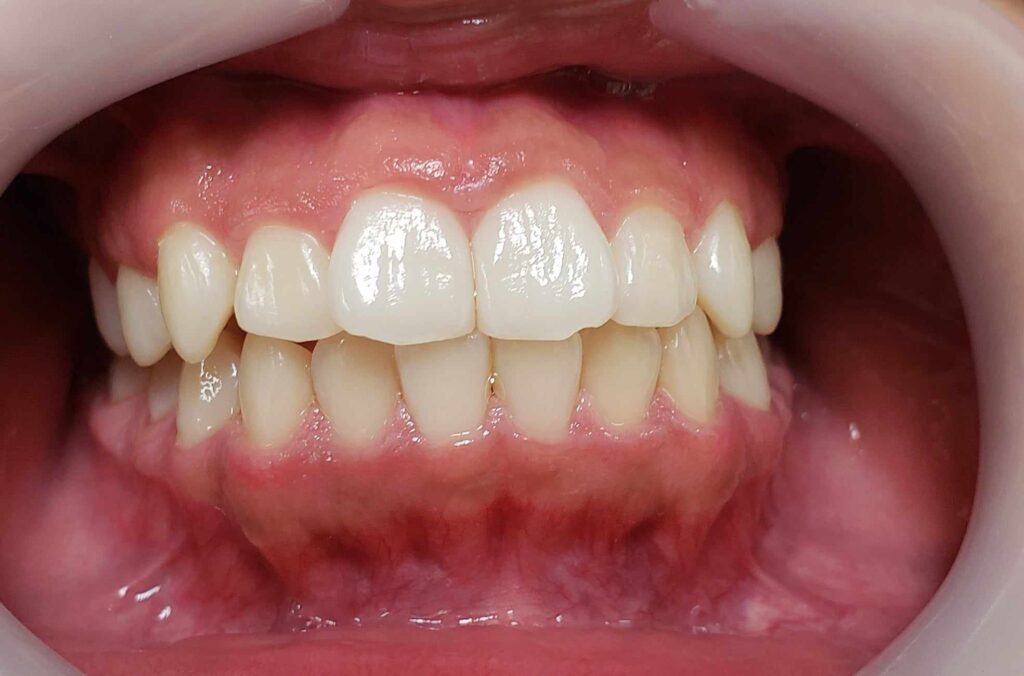

治療後

治療後のコメント

虫歯や歯肉炎の発症なく、まずまずの状態で1期治療を終了したと思います。もう少し上下顎拡大も考えましたが口が大きくなることを考慮して、最小限のディスキングで対応しました。親御さん、子供さん共に非抜歯での矯正を希望されましたが、今後シャープな口元を希望される場合、矯正の専門医で小臼歯4本抜歯ワイヤー矯正されるのも良いかもしれません。しかし舌房が狭くなり、噛みしめが誘発された方(歯周病の悪化、肩こり、知覚過敏、不定愁訴等)を数多く見てきているため、私は成人抜歯矯正(2期治療)をやるつもりはありません。(注、私は全ての抜歯矯正を否定しているわけではありません。正しく舌房の確保、舌のポジション、上下7番のコントロールを考えた矯正医が行うのは素晴らしいと思っています。)